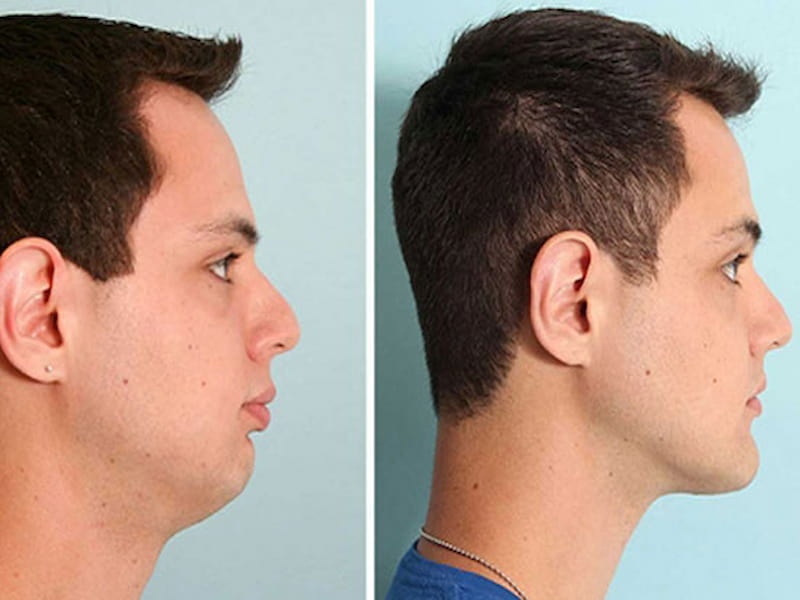

ایمپلنت زاویه فک به عنوان روشی برای اصلاح دندانهای برجسته و فک عقبی در افرادی که دارای اختلالات زاویه فک هستند، به کار میرود.

این روش به دلیل افزایش قابلیت تنظیم و دقت در اصلاح زاویه فک، مقرون به صرفهتر و کمتر دردناکتر از روشهای سنتی اصلاح فک است.

همچنین، این روش میتواند به عنوان یک راهکار برای اصلاح مشکلات بیمارانی که در سنین بالا هستند، مورد استفاده قرار گیرد.